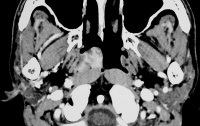

影像学诊断由三个方面组成:(1)X线检查;(2)CT检查;(3)MRI检查。

(七)鼻咽侧位片颅底片及CT检查 :每例患者均应常规作鼻咽侧位照片和颅底照片,疑及鼻旁窦中耳或其他部位有侵犯者,应同时作相应的摄片检查。有条件的单位应作CT扫描,了解局部扩展情况,特别需要掌握的是咽旁间隙的浸润范围,这对于确定临床分期以及制定治疗方案都极为重要。

(九)磁共振成象检查 :由于磁共振成象(MRl)可清楚显示头颅各层次脑沟脑回灰质白质和脑室脑脊液管道血管等,用SE法显示T1T2延长高强度图像,可以诊断鼻咽癌上额窦癌等,并显示肿瘤与周围组织关系。